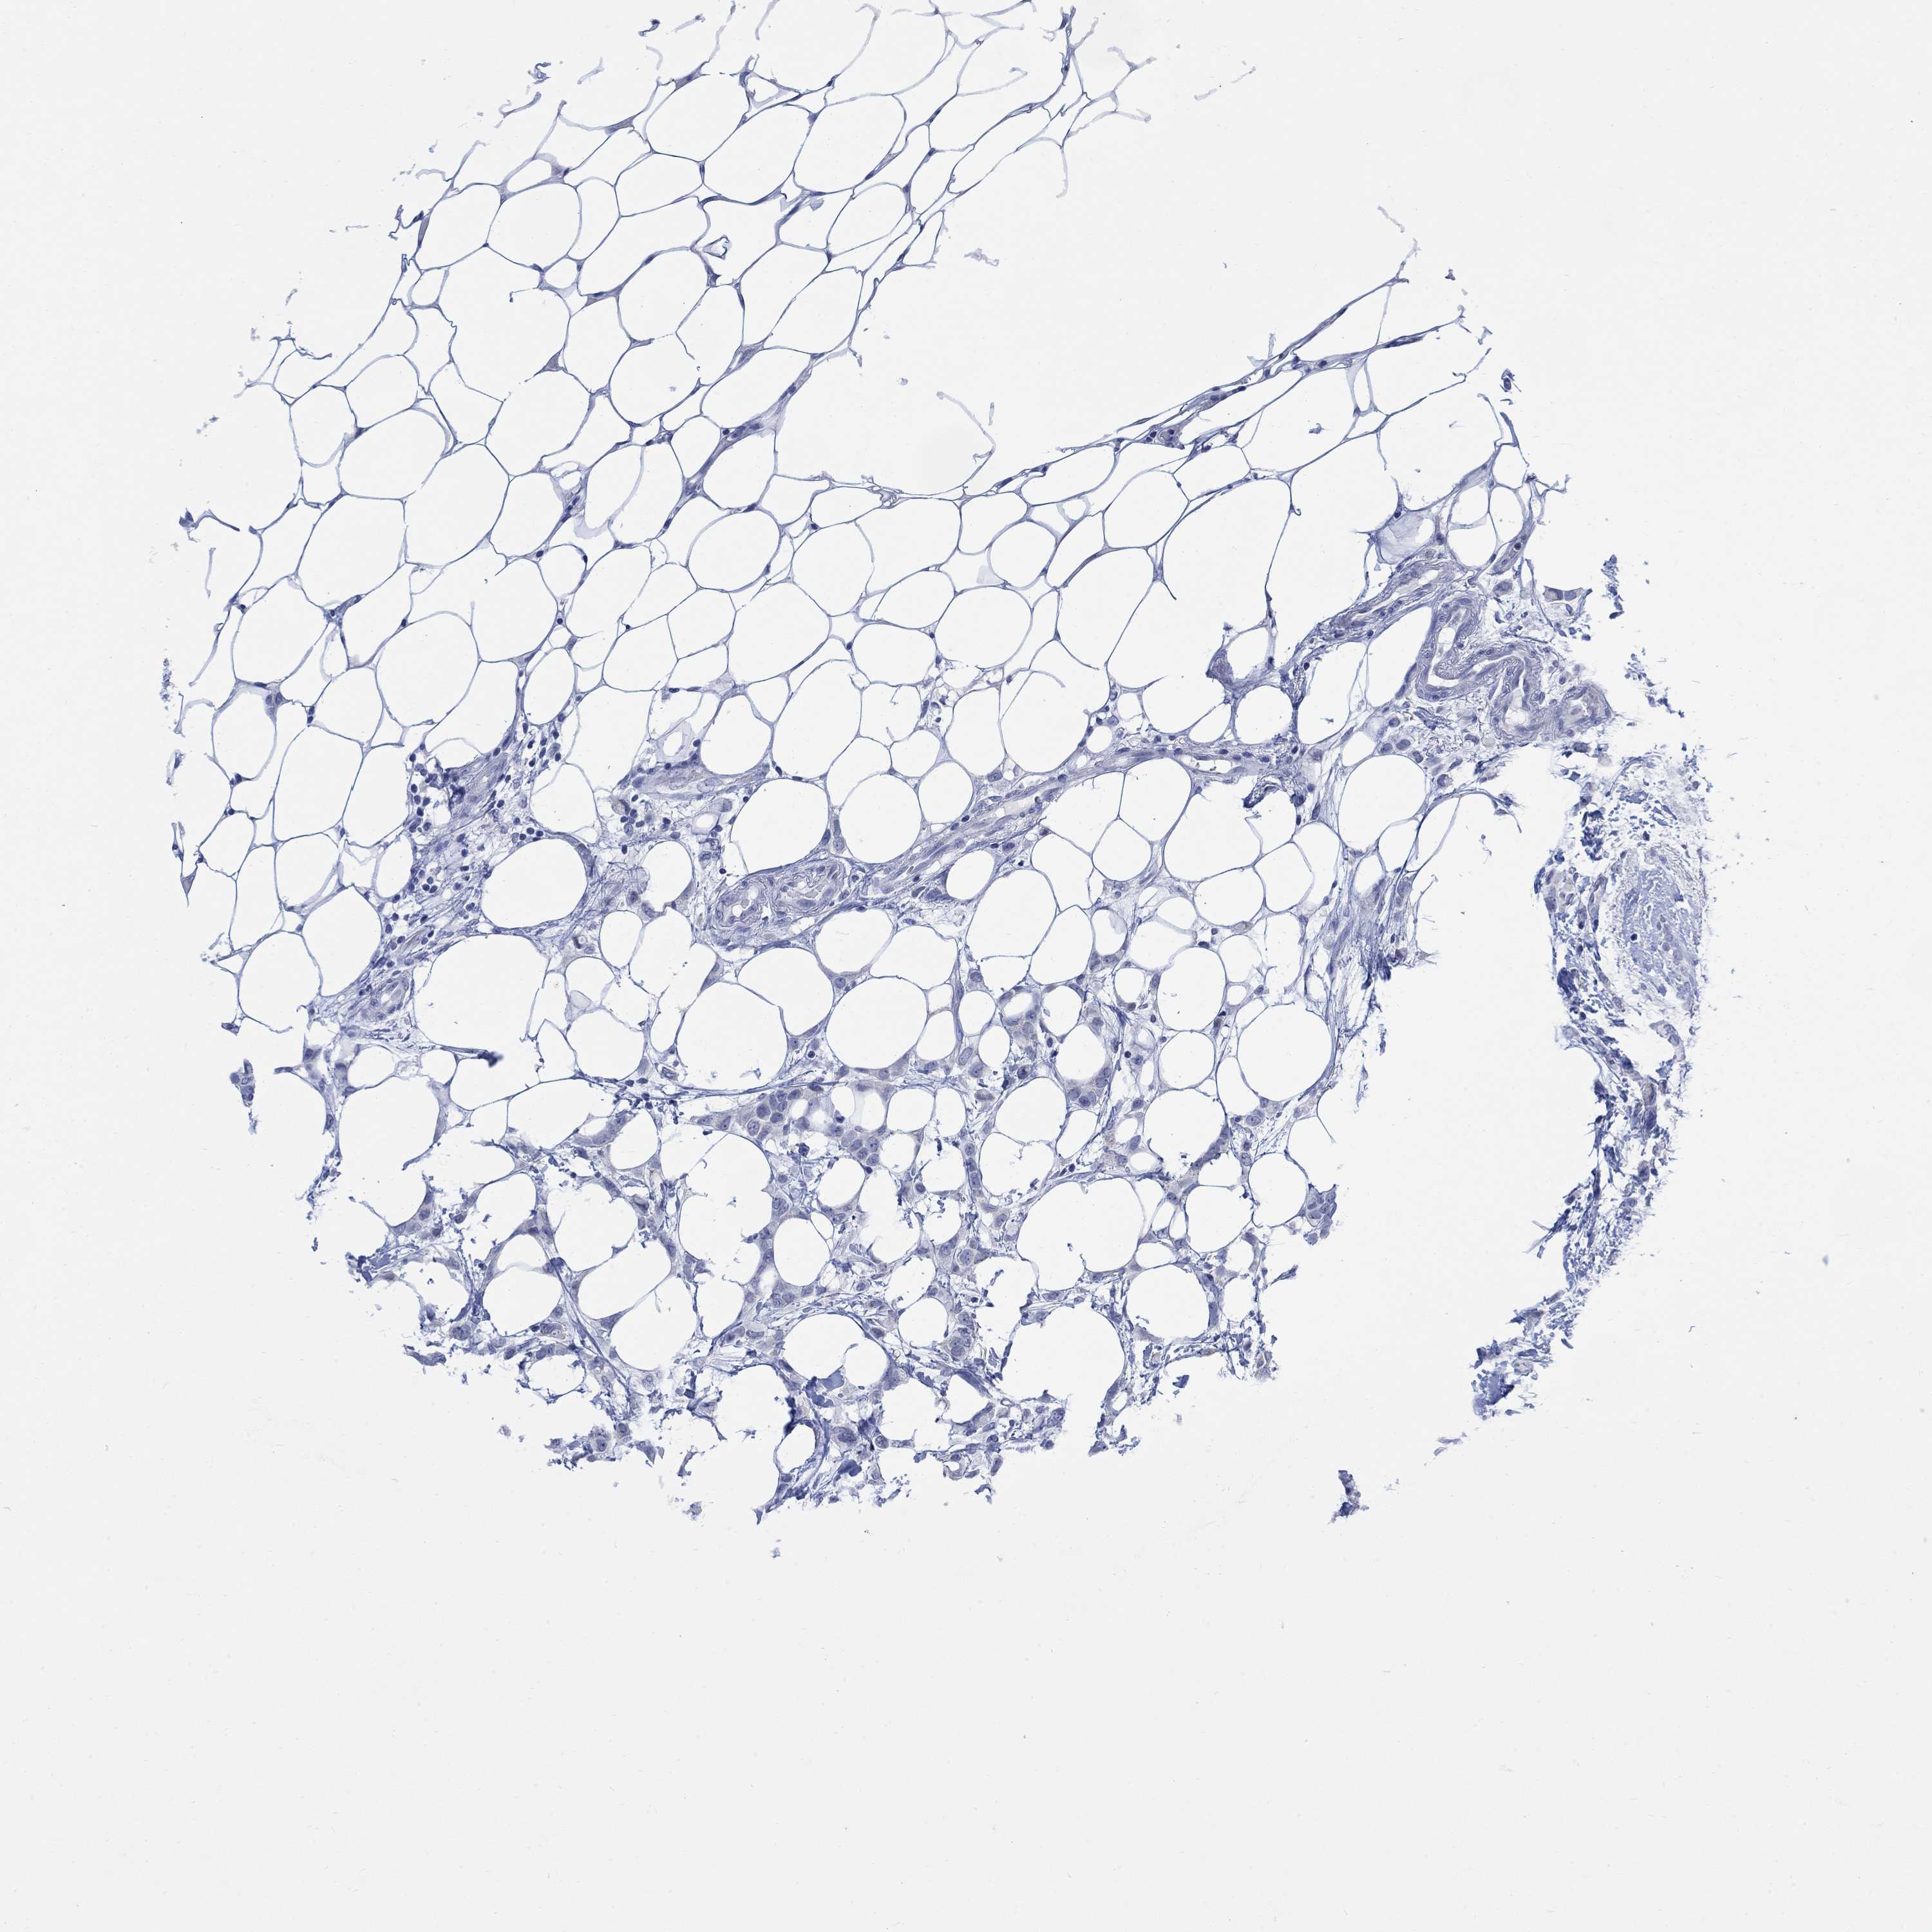

Breast cancer

Human cancer